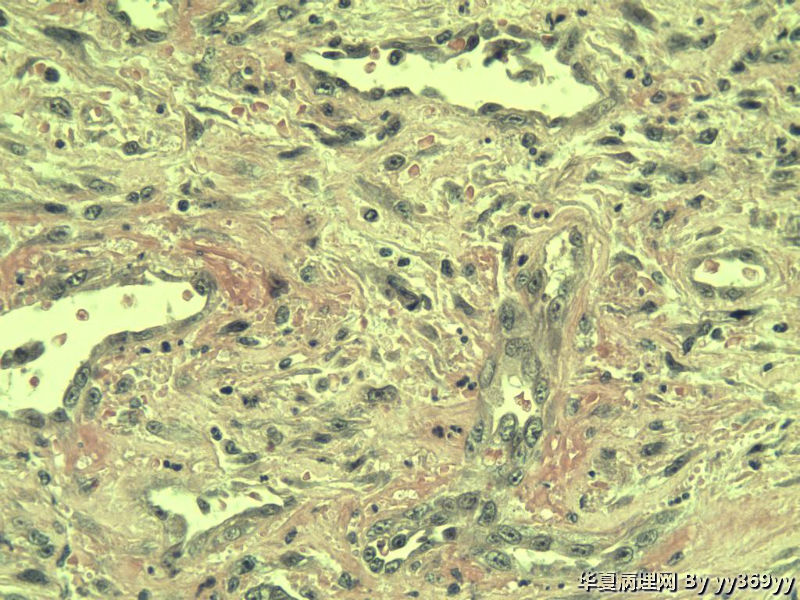

男 30岁 小肠一段,肠管严重粘连可见一体积为 2.5 × 2 × 1.5 cm3的肿块,切面灰白,实性,质中

从最后这几张高倍镜图看,淋巴样细胞弥漫性增生,很可能是淋巴瘤。

考虑炎性肌纤维母细胞瘤、炎性纤维性息肉、胃肠间质瘤,不考虑淋巴瘤

考虑炎性肌纤维母细胞瘤

这些都是增生的神经节细胞,在溃疡周围的正常粘膜里找找看有无肉芽肿

补取了几块 肌层纵行和横行平滑肌之间很多这种细胞 是什么??